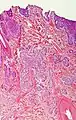

Differential diagnoses

| Differential diagnosis | Pathological Features | Image |

|---|---|---|

| Hair follicles | Peripheral sections may look like nests, but do not display atypia, nuclei are smaller, and serial sections will reveal the rest of the hair follicle. | ![]() |

| Squamous-cell carcinoma of the skin | Squamous-cell carcinoma of the skin is generally distinguishable by for example relatively more cytoplasm, horn cyst formation and absence of palisading and cleft formations. Yet, a high prevalence means a relatively high incidence of borderline cases, such as basal-cell carcinoma with squamous cell metaplasia (H&E stain at left in image). BerEP4 staining helps in such cases, staining only basal-cell carcinoma cells (right in image). | ![]() |

| Trichoblastoma | Absence of cleft, rudimentary hair germs, papillary mesenchymal bodies. | ![]() |

| Adenoid cystic carcinoma | Lack of basaloid cells disposed in peripheral palisades; adenoid-cystic lesion without connection to the epidermis; absence of artefactual clefts | ![]() |

| Microcystic adnexal carcinoma | Bland keratinocytes, keratin cysts, ductal differentiation. BerEp4- (in 60% of cases),[33] CEA+, EMA+ | |

| Trichoepithelioma[notes 1] | Rims of collagen bundles, calcification, follicular/sebaceous/infundibular differentiation and cut artefacts. Cytokeratin (CK)20+, p75+, Pleckstrin homology-like domain family A member 1 + (PHLDA1+), common acute lymphoblastic leukemiaantigen + (CD10+) in tumor stroma, CK 6-, Ki-67- and Androgen Rceptor- (AR-) | ![]() |

| Merkel cell carcinoma | Cells arranged in a diffuse, trabecular and/or nested pattern, involving also the subcutis. Mouse Anti-Cytokeratin (CAM) 5.2+, CK20+, S100-, human leukocyte common antigen- ( LCA-), thyroid transcription factor 1- (TTF1-) | ![]() |